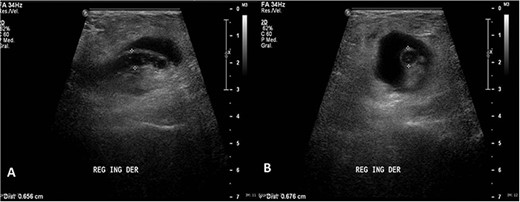

Ultrasound was performed with a Philips iU22 ultrasound using a 9 MHz linear transducer. A well-defined cystic mass was observed over the area. Right in the middle, a tubular image that terminated in a blind-ended tip in the longitudinal plane (Fig. 1A) and a target appearance on the cross-sectional plane (Fig. 1B) consistent with the appendix were demonstrated. The appendix measured 0.63 and 0.72 mm, discreetly above normal range, and it showed hypoechoic thickening of the mucosal layer. Color Doppler flow of the tip (Fig. 2) and adjacent soft tissue showed inflammatory changes. The patient presented pain on compression with the transducer. The surrounding fat tissue presented increased echogenicity suggesting inflammatory tissue. The preoperative surgical diagnosis was a strangulated inguinofemoral hernia. However, the findings were reported as acute appendicitis within an inguinal hernia sac. Inguinal hernioplasty with inguinal exploration and repair of an inguinofemoral hernia and resection of intestinal contents were performed (Fig. 3).

(A) Longitudinal ultrasound of the groin area showing a well-defined cystic mass with a central tubular image that terminated in a blind-ended tip. (B) Cross-sectional ultrasound showing the appendix more than 6 mm in diameter with echogenic surrounding fat soft tissue suggesting inflammatory changes.